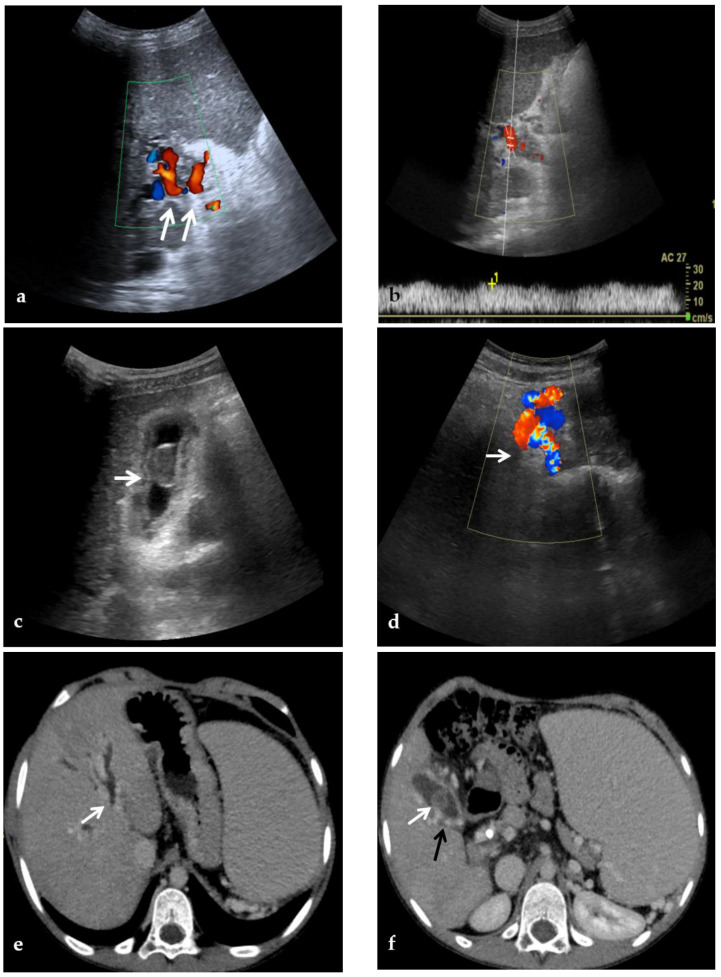

Portal biliopathy is defined as the presence of abnormalities of the extrahepatic and intrahepatic bile ducts and gallbladder walls in patients with noncirrhotic/non-neoplastic PVT [2] (Figure 2).

Figure 2.

CDUS, CT, and MR images of a 9-year-old male with intrahepatic and extrahepatic cavernous transformation of the portal vein and portal biliopathy who presented with jaundice and cholangitis. (a) A Color-Doppler Ultrasound image shows multiple collateral vessels at the porta hepatis (arrows) and the absence of the main portal trunk. (b) Spectral evaluation of the major collateral vein of the cavernoma shows an hepatopetal flow with a velocity within normal ranges, which could potentially be misleading by an unexperienced operator. (c) An ultrasound image scan through the gallbladder shows a mildly echogenic endoluminal stone in the gallbladder (arrow). (d) Color-Doppler Ultrasound image shows multiple dilated collateral cavernous vessels in the gallbladder fossa (arrow). (e) Portal phase axial CT image shows dilation of intrahepatic biliary ducts (arrow) due to extrinsic compression of the common biliary duct by the cavernoma. (f) A caudal axial CT view in the portal venous phase shows a mildly hyperdense stone in the gallbladder (white arrow) which is surrounded by dilated cavernous vessels (black arrow). (g) Axial T2-weighted MR image shows intrahepatic biliary dilatation (arrows) due to common biliary duct extrinsic obstruction by prominent paracholedochal collateral cavernous vessels. (h) A caudal axial T2-weighted MR view shows wall thickening of the gallbladder (white arrows) which contains other multiple small gallstones in the fundus (black arrow).

Although radiologic manifestations of portal cavernoma biliary damage are described in up to 100% of patients with extrahepatic PVT, most of them are initially asymptomatic. In one study [43], only 1 of 20 patients had choledocholithiasis, whereas, in another study [44], biliary changes were associated mainly with biochemical abnormalities.

However, progressive portal cavernoma cholangiopathy may become symptomatic in 5% to 38% of patients presenting with jaundice, pain, recurrent cholangitis, and cholecystitis, typically 8–10 years after diagnosis, and leads to severe complications, including secondary biliary cirrhosis in the case of prolonged bile duct obstruction [45,46].

Biliary abnormalities are common in PVT because paracholedochal and paracholecystic veins form the portoportal collaterals to bypass the obstructed segment of the portal vein. Biliary abnormalities may be explained either by compression of bile ducts by prominent paracholedochal and epicholedochal collateral vessels (indentations and wall irregularities) or ischemic injury of the bile ducts as a result of thrombosis of veins draining the bile duct (leading to ischemic stricture development). Biliary stricture is a frequent finding on MR examinations in the setting of portal cavernoma biliopathy, affecting up to 93.7% of patients [47].

The ultrasonographic diagnosis of PVT relies on the presence of echogenic material obstructing the lumen of the vessel and the complete or partial absence of flow in the portal vein at color flow Doppler imaging [51] (Figure 3). As the chronic thrombus ages and calcifies, CDUS may show areas of increased echogenicity. In addition, the collateral veins from cavernous transformation around the segments of PVT display a serpiginous mixed-color pattern on CDUS and are anechoic on gray-scale imaging [39,52]. The appearance of the portal cavernoma has been described as a “spongelike mass”, a distinctive tangle of tortuous vessels in the porta hepatis characterized by hepatopetal flow with loss of normal portal phasicity [2] (Figure 2). However, discriminating cavernous collaterals from the portal vein in children with PVT can be very difficult.

In portal biliopathy CDUS provides additional information regarding the presence of gallbladder varices, observed in about 35% of patients. Gallbladder varices appear as tortuous, dilated vessels in or around the wall of the gallbladder or in the gallbladder fossa. Moreover, ultrasound can detect the presence of cholelithiasis caused by biliary obstruction secondary to portal biliopathy: gallstones are characteristically echogenic and demonstrate posterior acoustic shadowing regardless of the gallstone composition [48] (Figure 2).